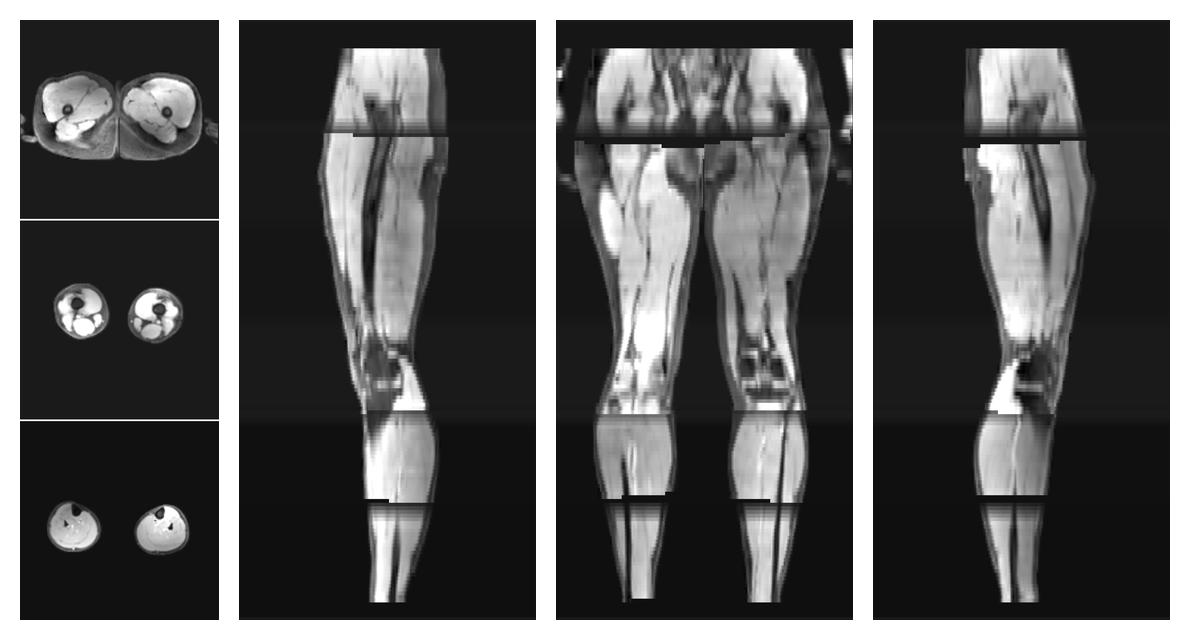

• Fractional anisotropy

IVIM corrected whole leg muscle fractional anisotropy obtained from diffusion tensor imaging.